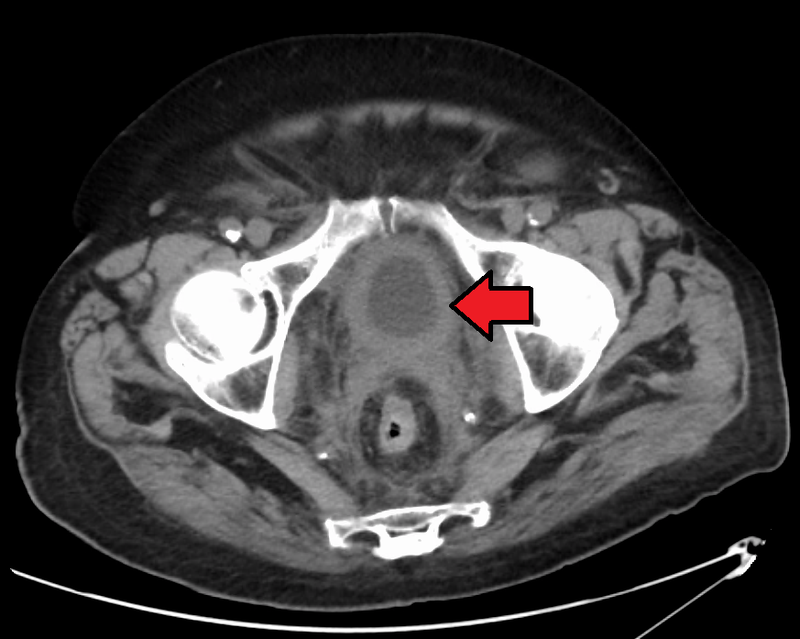

Wilms Tumor

Wilms tumor is a malignant kidney tumor composed of primitive glomeruli, tubules, and stromal cells blastema which is an immature kidney mesenchyme.

The average age of a child who develops a Wilms tumor is 3-years-old.

Symptoms of Wilms tumor include:

- Large mass

- Unilateral flank mass

- Hematuria

- Hypertension brought on by renin secretion

Wilms tumor is associated with WT1 mutation, especially in syndromic cases.

WAGR syndrome is the disease called for its features, which include:

- Wilms tumor

- Aniridia

- Genitourinary abnormalities

- Intellectual impairment

Beckwith-Wiedemann syndrome is another disease associated with Wilms tumor, and includes:

- Wilms tumor

- Neonatal hypoglycemia

- Muscular hemihypertrophy

- Organomegaly